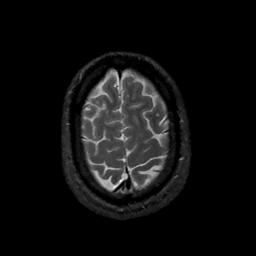

MR Study #11, May 5, 1991 -- Slice #43

[Home][Help][Clinical][Tour 1][Tour 2] Slice 43